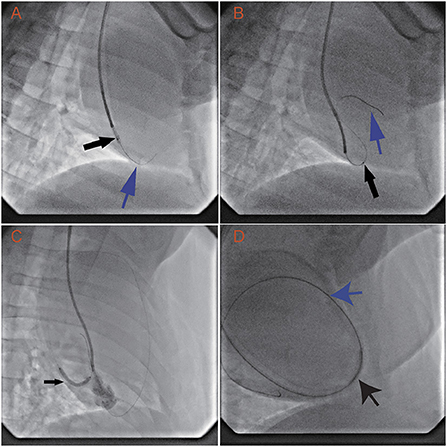

In all animals, the RV was successfully punctured with the back end of a 0.014-inch guidewire and 1.8 Fr microcatheter. The guidewire and microcatheter easily punctured through the RV into the pericardial space. Once the back end of the guidewire contacted the ventricular wall, puncture into the pericardial space took 7.8 ± 3.9 s. The guidewire tracked along but was not used to puncture the parietal pericardium (Figure 2A). The microcatheter was advanced along the guidewire into the pericardial space in several seconds (Figure 2B).

Figure 2

Transvenous puncture of the acute margin of the RV and confirmation of its safety margin by dilation of the puncture hole. The procedure uses an LAO projection of 30°, while the animals are in a left recumbent position. (A) With the support of the 1.8 Fr Finecross microcatheter (black arrow) and 6 Fr SAL 0.75 guiding catheter, the back end of the Sion wire (blue arrow) is used to puncture the middle of the acute margin of the right ventricle. (B) After the 1.8 Fr Finecross microcatheter (black arrow) is advanced into the pericardial space, the front end of the wire (blue arrow) is navigated into the pericardial space. (C) The puncture hole is dilated with a 2.5 × 23 mm balloon (12 atm × 15 min). (D) A 6 Fr JR 3.5 guiding catheter, with a 0.035-inch wire, is placed through the right ventricular wall into the pericardial space.

The RV can spontaneously control bleeding after dilation with a 2.5-mm balloon for 15 min under anticoagulation. The first two swine underwent serial dilation with 2-, 2.5-, and 3-mm balloons and showed no observable signs of pericardial effusion. However, the third swine displayed minor pericardial effusion (echocardiography showed effusion with a depth of 4 mm in diastole) after dilation with a 3.0-mm balloon. The animal's circulation was not compromised, and drainage was not needed. To provide a solid safety margin, the 3-mm balloon was not tested in the remaining animals. Then, the remaining swine and all the dogs received dilation with a 2.5-mm balloon only (Figure 2C). After the 2.5-mm balloon was withdrawn from all the animals, echocardiography was performed and showed no signs of pericardial effusion. These results suggest that the acceptable dilation size is no more than 2.5 mm and that the RV wall can spontaneously control bleeding under anticoagulation.

The RV also has the capacity to control bleeding after a long dilation time. The 6 Fr catheter was placed in the pericardial space via the RV wall puncture hole (Figure 2D) in nine swine and five dogs. Three days later, the catheter was withdrawn. Monitoring via echocardiography did not show any signs of pericardial effusion. The hearts were inspected after the procedure. The pericardial spaces were clean, and there were small (~1 mm), dull, red plugs in the puncture holes.